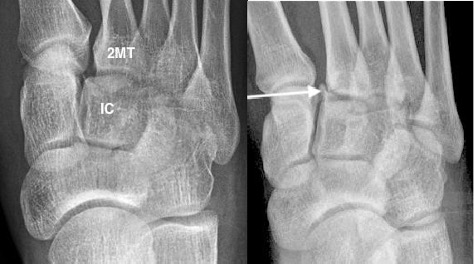

Lisfranc fracture

- Fracture-dislocation of the tarsometatarsal joints

- Key to normal alignment:

- medial border of the 2nd MT should line up with the medial border of the intermediate cuneiform on the AP view

- medial margin of the 3rd MT should line up with the medial margin of the lateral cuneiform on the oblique view

- May be missed if subluxation is minimal

- Gap > 2mm between bases of 1st and 2nd MTs is abnormal

- ‘Fleck sign’ indicates small avulsion fragment, from lateral edge medial cuneiform or medial 2nd MT base

Lisfranc fracture with widening between 1st and 2nd MT bases, malalignment of the 2nd metatarsal (2MT) and intermediate cuneiform (IC). Fleck sign (arrow) indicating small avulsion from 2nd MT base